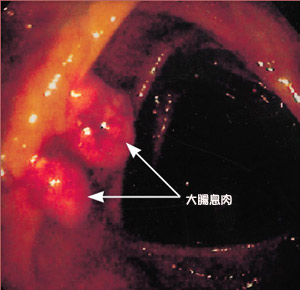

結腸直腸腺瘤① 脆性:在檢查時,以窺器或器械觸及時極易出血者,多為惡性息肉。反之則為良性。

② 潰瘍:息肉一般情況下無潰瘍,當惡變時,即可形成潰瘍,特別是帶蒂的息肉一般不會引起潰瘍,一旦發生潰瘍,則表明其有惡性改變。

③ 活動性:堅實牢固、無蒂的息肉易惡變;而帶蒂具有活動性的則惡變相對較低。

④ 外形:有分葉的息肉易惡變,光滑圓潤的則少。

⑤ 基底:息肉基底大,頭小者極易惡變。

⑥ 類型:有蒂的多是管狀腺瘤,相對癌變率較低。

⑦ 大小:息肉增大或息肉較大的易惡變,息肉無明顯增大的,則較少惡變。